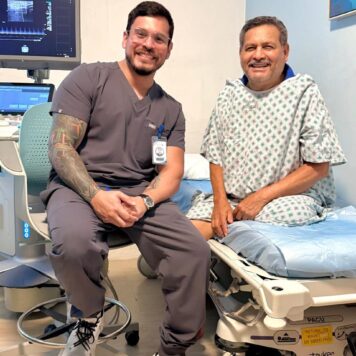

Dr. Carlos Rodríguez

Radiólogo Intervencionista

El Dr. Carlos Rodríguez es un destacado radiólogo intervencionista, formado en la Universidad Nacional Autónoma de México (UNAM), una de las instituciones académicas más prestigiosas de Latinoamérica. Complementó su formación con un Diplomado en Procedimientos Endovasculares por la Universidad Anáhuac, donde desarrolló una sólida base en diagnóstico vascular, cirugía endovascular y manejo avanzado de la patología arterial periférica.

A su regreso a Nicaragua, el Dr. Rodríguez se ha consolidado como uno de los referentes nacionales en radiología intervencionista, diagnóstico vascular de alta precisión y salvamento del pie diabético isquémico, aportando soluciones médicas innovadoras y mínimamente invasivas.